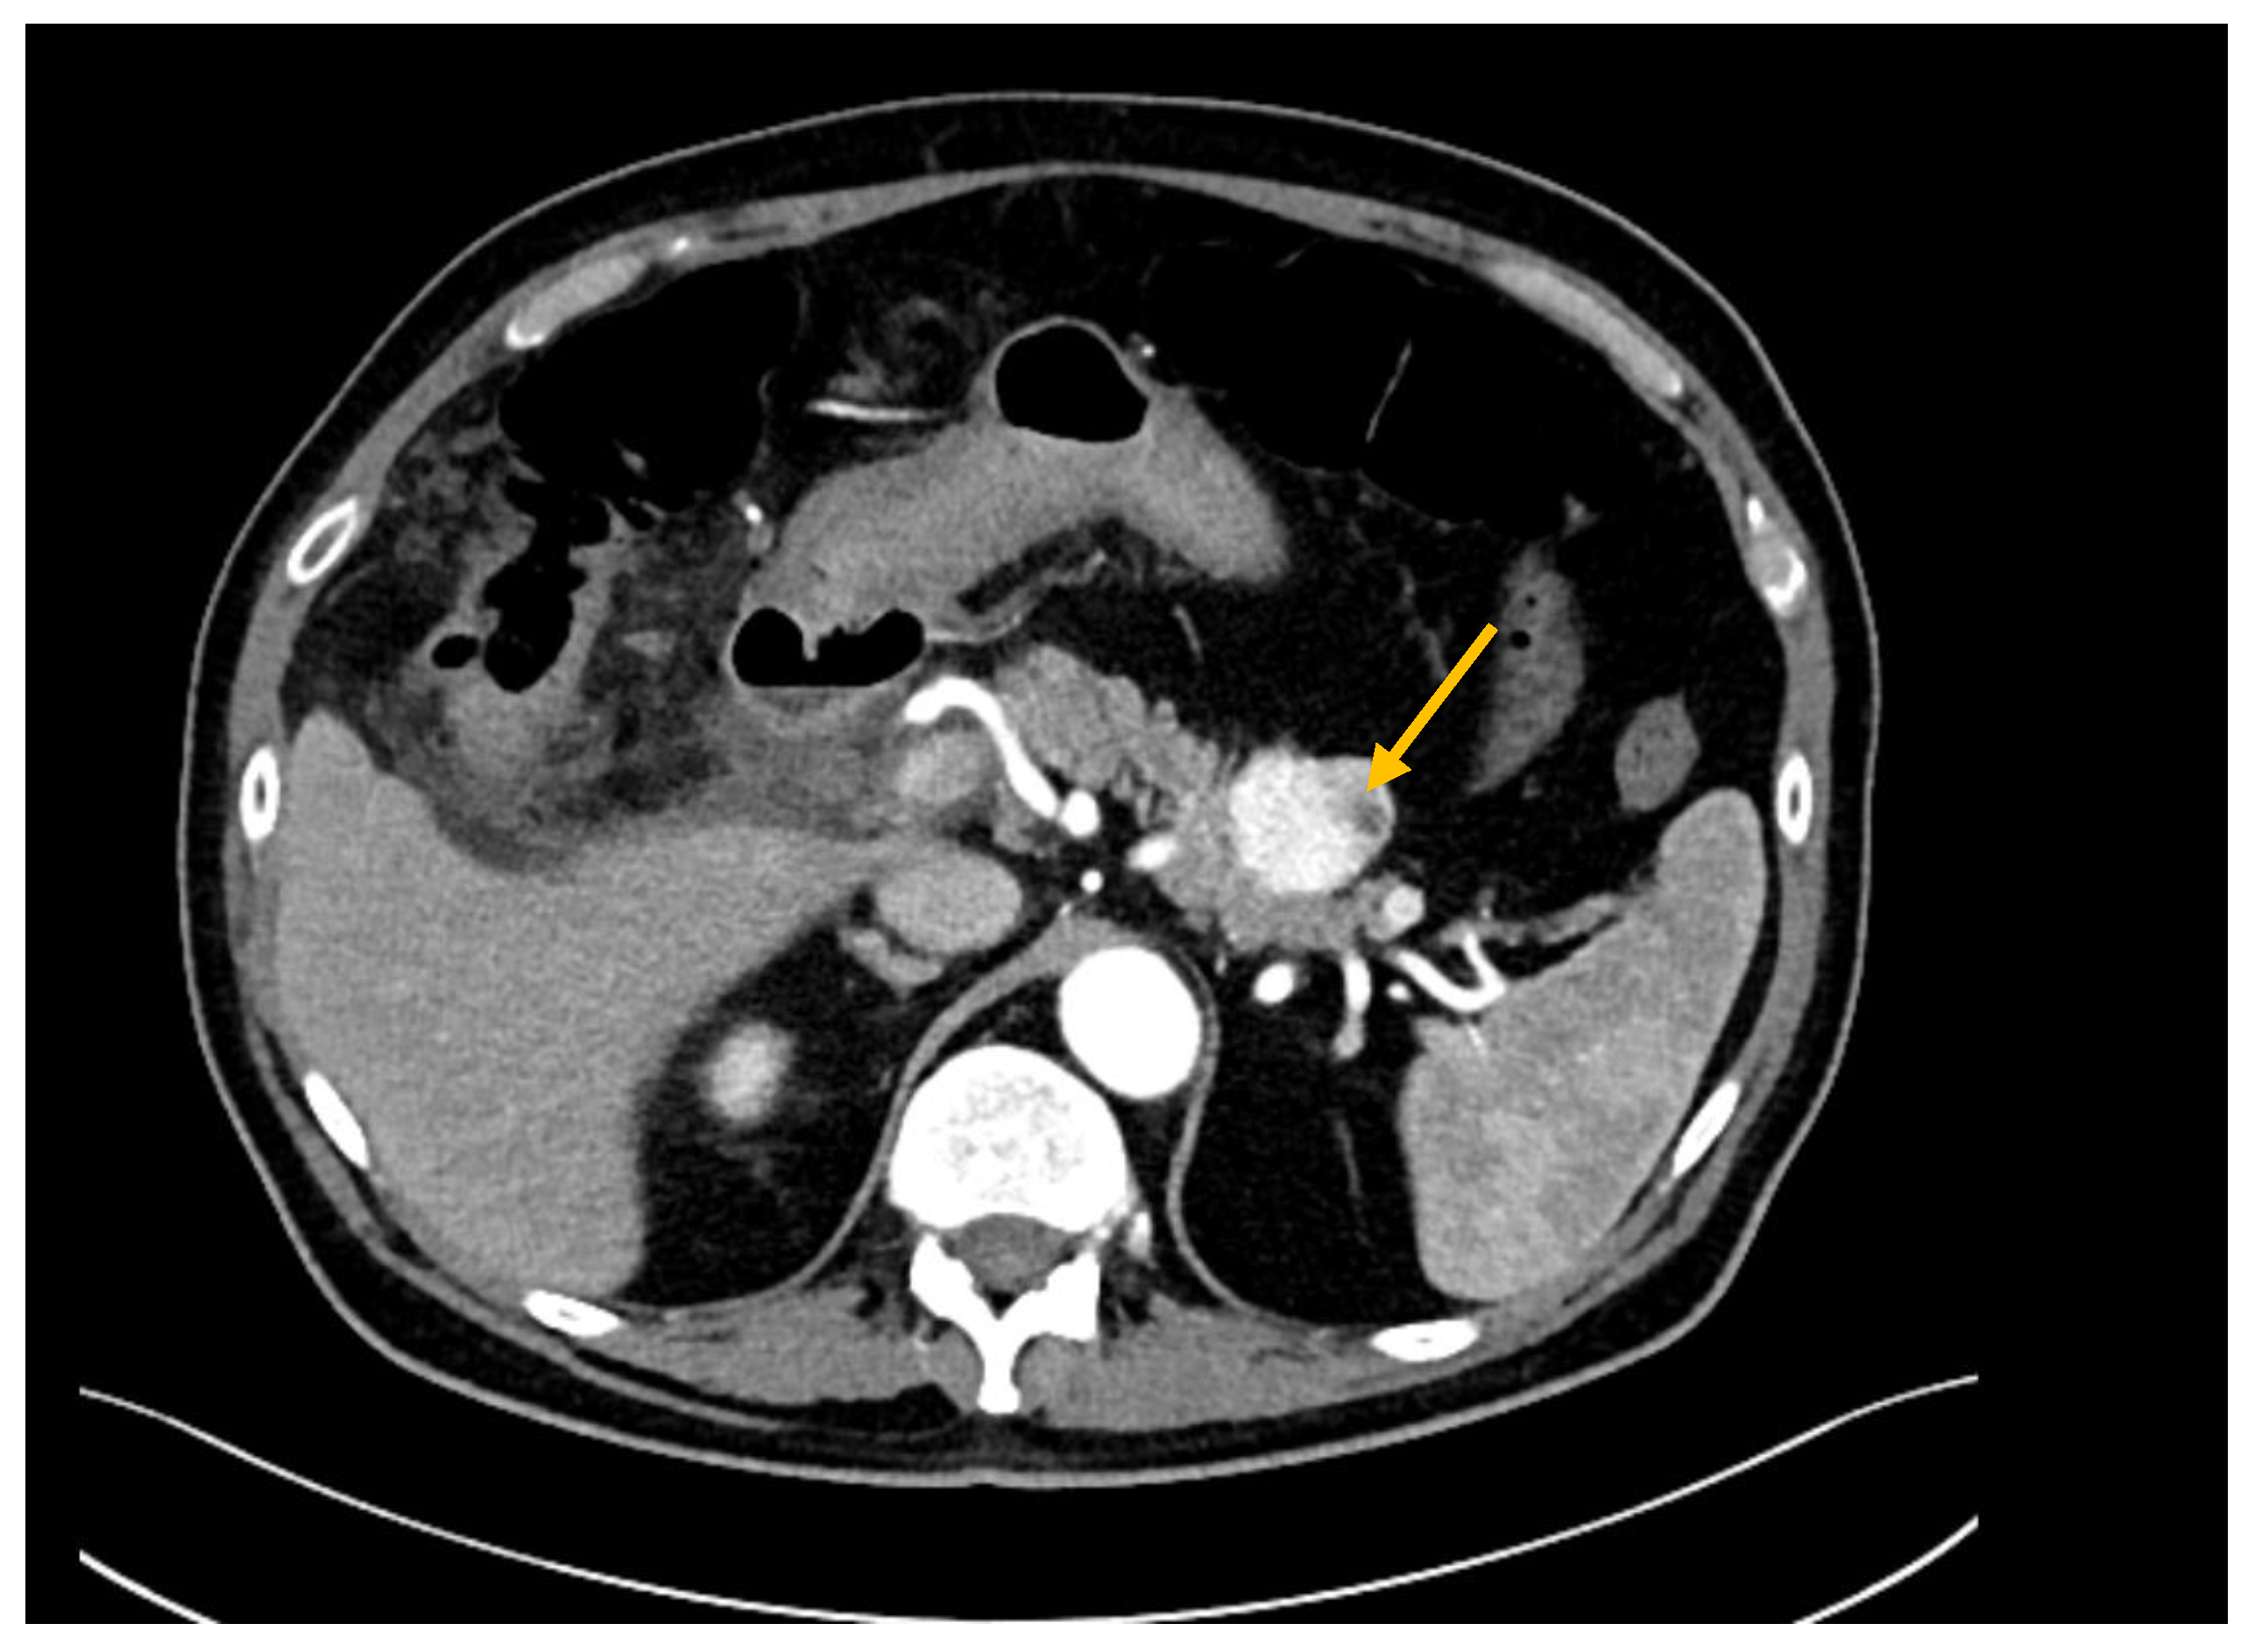

3.2. Diagnostic Work-Up

- Vincenzi, M.; Pasquotti, G.; Polverosi, R.; Pasquali, C.; Pomerri, F. Imaging of pancreatic metastases from renal cell carcinoma. Cancer Imaging 2014, 14, 5. [Google Scholar] [CrossRef]